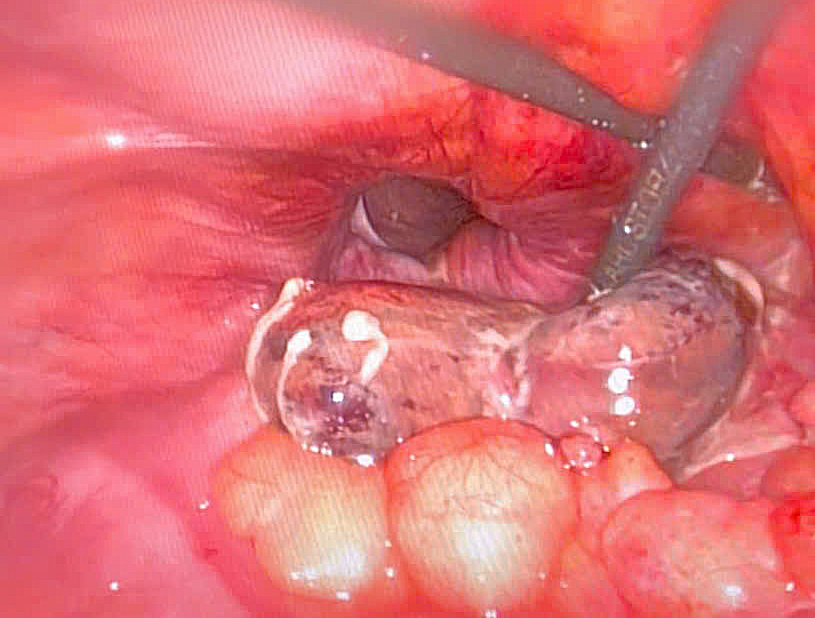

Kíp mổ cấp cứu khoa Ngoại xử trí khối thoát vị bẹn trái bị nghẹt cho bệnh nhân

Hình ảnh đại tràng bị hoại tử và lỗ thoát vị qua nội soi